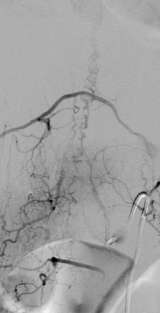

Figure 2: Spinal Dural AVF

Unlike the vascular malformation on or in the spinal cord, dural or epidural AVFs (Figure 2) are an acquired condition, and are commonly discovered in mid 50s males. The symptoms include progressive weakness and numbness in the lower extremities, bowel bladder disturbance, back pain, and sexual dysfunction.

MRI and CT can detect spinal vascular malformations. However, spinal catheter angiography is oftenrequired to further classify the lesion. Making an accurate diagnosis / classification is the first step to compose the best management plan for the lesion.